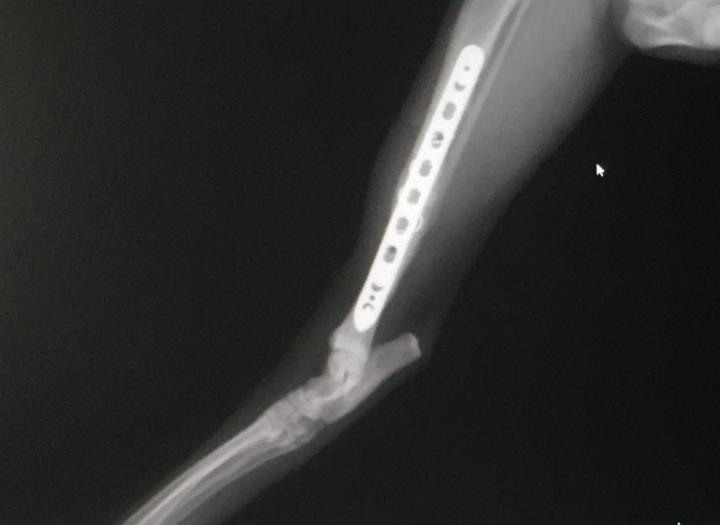

2021年3月プレート抜去手術(1回目)から1週間。

今回のレントゲン かなり良くなってる。

でもこの角度だとボルト穴の様子がわからん。